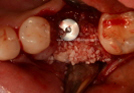

Clinical Cases

• Case1